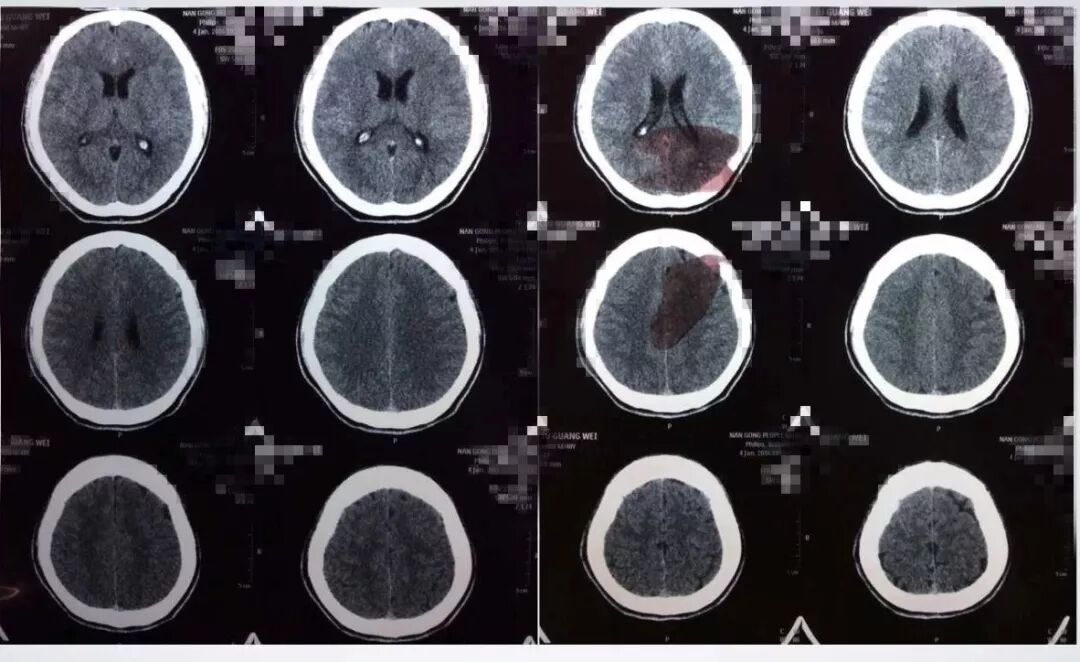

发病后9天CT